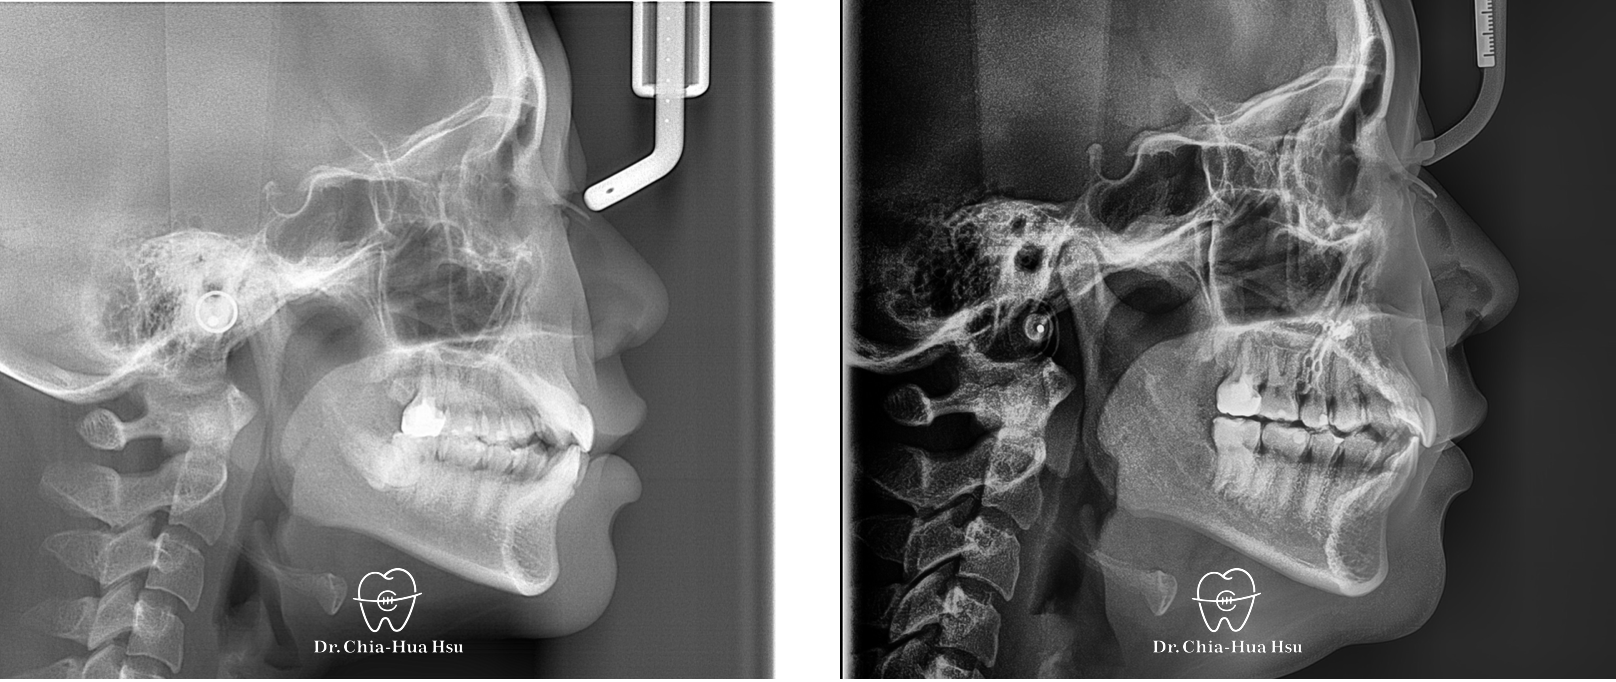

- 問題分析:患者是標準的骨骼一類咬合(Skeletal Class I)伴隨齒列擁擠。

- 治療方式:雖然患者的齒列凌亂程度甚為嚴重,但是考量到患者外觀、門牙可以往外移動一些,而且尚有智齒空間可以退後,因此最後選擇隱適美治療,不拔小臼齒,利用骨釘與骨板退後齒列,同時讓門牙向外推出去一些,並撐寬牙弓以獲得空間。

治療前

治療後